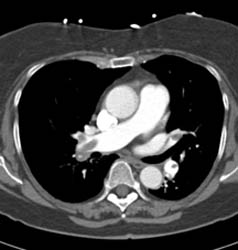

Breast Implants and Thymoma